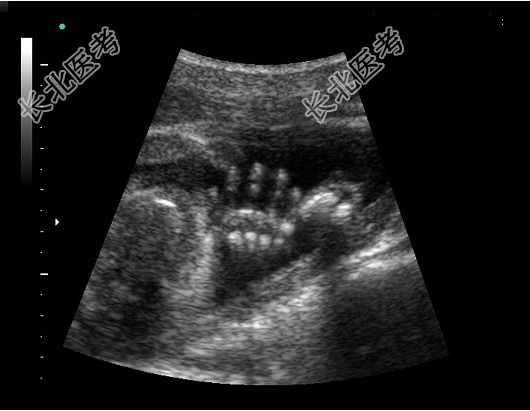

- 单项选择题如图,超声显示的是胎儿的哪个部位( )

A、颈部

B、脚

C、腿

D、腹部

E、手